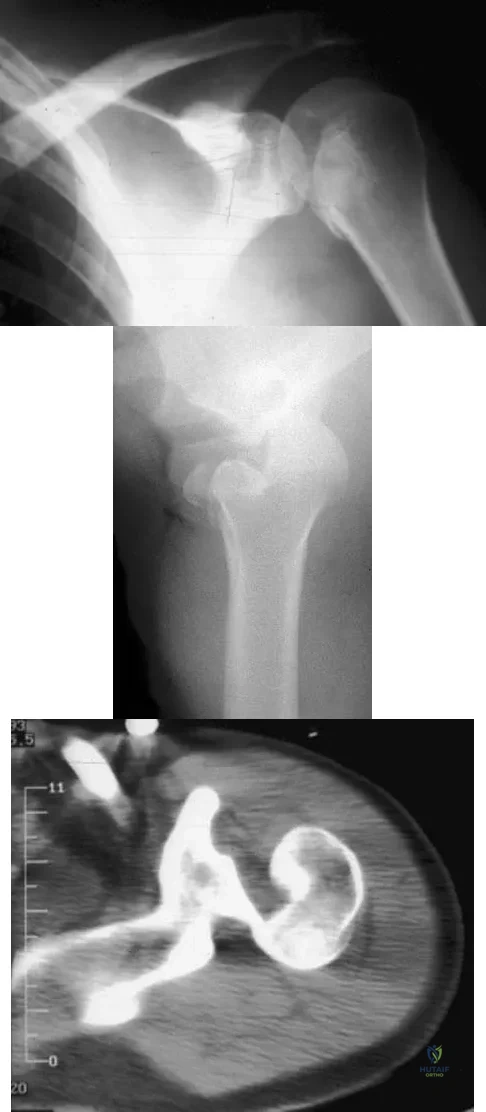

Examination of the shoulder seen in Figure 52 shows atrophy and tenderness of the infraspinous fossa and profound weakness in external rotation. The supraspinous fossa shows normal muscle bulk. What is the most likely cause of this condition?

Figures 11a and 11b show the AP and lateral radiographs of a 32-year-old patient on hemodialysis who has increasing elbow pain and a visibly growing mass over the extensor surface. Figure 11c shows the photomicrograph of the biopsy specimen. What is the most likely diagnosis?

Figure 13 shows the radiographs of a 20-year-old intercollegiate basketball player who was injured 6 weeks prior to the start of the season. What is the most appropriate treatment?

Figures 11a and 11b show the AP and lateral radiographs of a 32-year-old patient on hemodialysis who has increasing elbow pain and a visibly growing mass over the extensor surface. Figure 11c shows the photomicrograph of the biopsy specimen. What is the most likely diagnosis?

Figures 36a and 36b show the MRI scans of a patient who has shoulder weakness. What is the most likely diagnosis?

A 21-year-old patient has had pain and a marked decrease in active and passive shoulder motion after having had a seizure 2 months ago as the result of alcohol abuse. Current AP and axillary radiographs and a CT scan are shown in Figures 26a through 26c. Management should consist of

Figure 5 shows the radiograph of a 10-year-old girl who reports chronic shoulder pain after her gymnastics classes. Examination reveals pain on internal and external rotation but no instability. What is the most likely diagnosis?

A 79-year-old woman with polyarticular rheumatoid arthritis has had progressively increasing right shoulder pain for the past year, and nonsurgical management has failed to provide relief. Her neurologic examination is entirely normal, but she is unable to elevate her arm against gravity. An AP radiograph is shown in Figure 13. Treatment should consist of

A 21-year-old patient has had pain and a marked decrease in active and passive shoulder motion after having had a seizure 2 months ago as the result of alcohol abuse. Current AP and axillary radiographs and a CT scan are shown in Figures 26a through 26c. Management should consist of